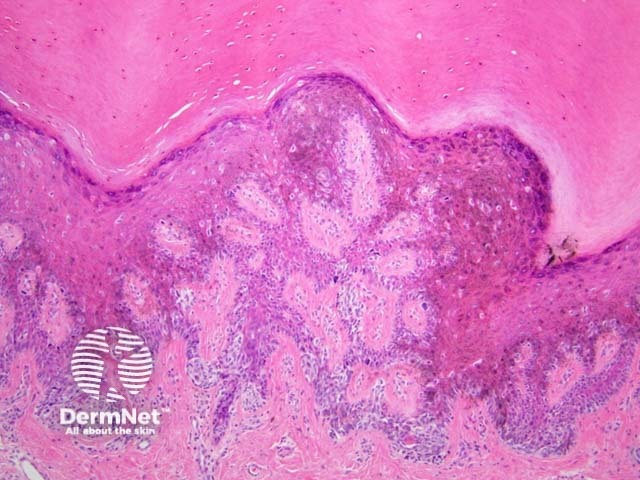

Acral lentiginous melanoma may have spindled or epithelioid cellular morphology. Changes may be subtle with scattered atypical melanocytes located close to the basal layer. Epidermal acanthosis, elongation of rete ridges and extension along sweat ducts are typical features (figure 23).

Figure 23